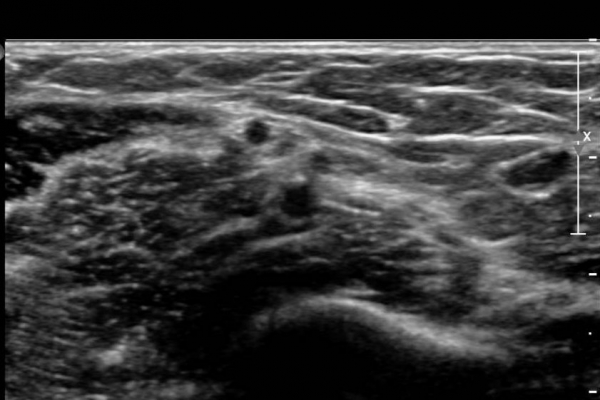

°üÂûµÈ´Ù(»çÁø 3 , 4,  5,).

Á¤Á߽Űæ Á¾´Ü¸é °Ë»ç¿¡¼­µµ  Á¤Áß ½Å°æ ÀϺΠ´Ù¹ßÀÇ ¹æÃßÇü Àú¿¡Ä¿ ºÎÁ¾ÀÌ °üÂûµÈ´Ù(»çÁø 6, 7).